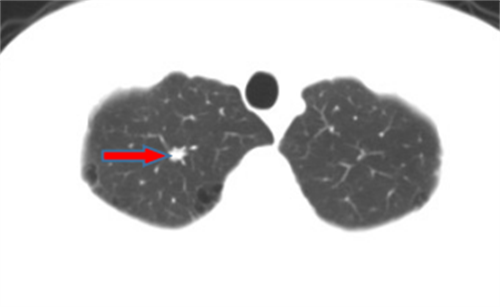

王女士,57岁,体检发现右下肺结节2月,术后病理诊断肺结节为肺隐球菌病。

李先生,45岁,发现右上肺结节2年,近期长大,术后病理诊断肺结节为炎性假瘤。

龙先生,65岁,体检发现右下肺结节,术后病理诊断肺结节为硬化性血管瘤。

郭女士,63岁,体检发现右下肺结节20天,术后病理诊断肺结节为浸润性腺癌。

王女士,65岁,体检发现右上肺磨玻璃结节16天,术后病理诊断肺结节为浸润性腺癌。

王女士,52岁,体检发现右上肺磨玻璃结节7月,术后病理诊断肺结节为原位腺癌。

王女士,35岁,新冠核酸检查阳性7天,胸部CT检查左上肺磨玻璃影,考虑新冠病毒性肺炎。